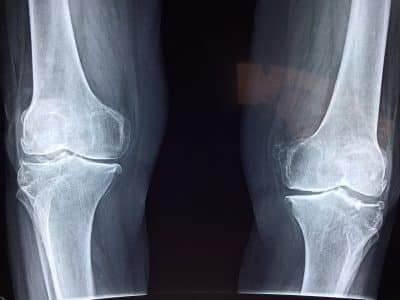

Восстановление каждого человека индивидуально, что зависит от его физиологических особенностей и типа полученной травмы. Речь идет о легких ортопедических травмах, таких как растяжения мышц во время занятий спортом или травмы спины в процессе физической работы. При более серьезных повреждениях необходимо следовать строгим указаниям врача.